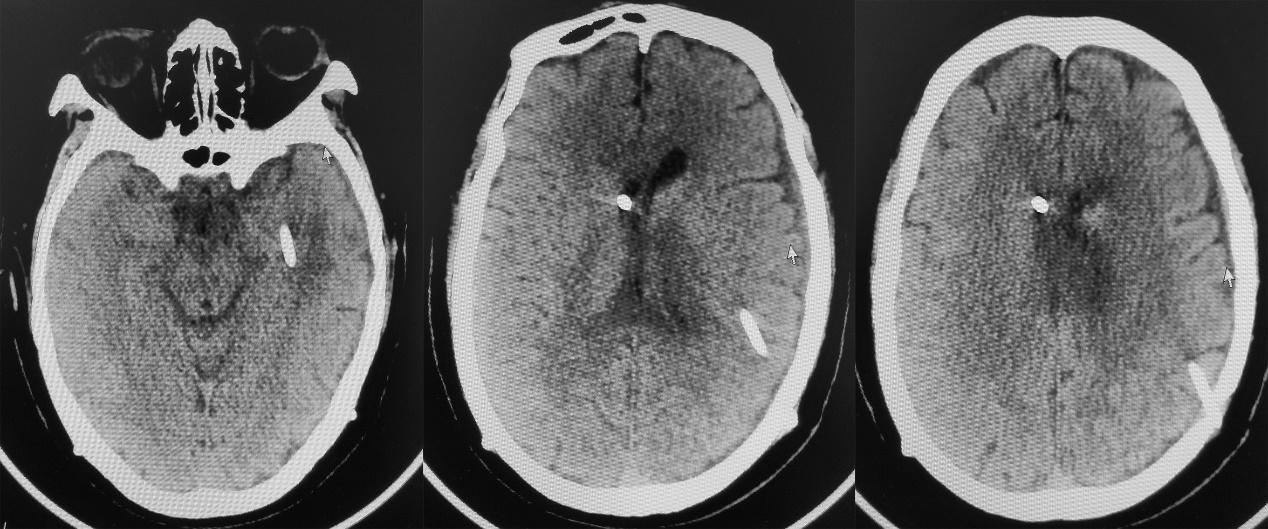

入院当天复查头CT见右侧脑室额角内分流管,脑室扩张;左侧颞角可见外引流管( 图-32 )。

图-32: 2021年2月10日头CT

于入院当天行脑室腹腔分流管拔除+脑室外引流术,同时拔除了左颞角引流管。术后第2天即2021年2月12日,复查头颅CT见引流管位置满意,右侧脑室仍稍扩张( 图-33 )。患者病情平稳,无发热,神志模糊。

图-33: 2021年2月12日头CT

术后第8天,即2021年2月18日,复查头颅CT见右侧脑室缩小,左侧脑室稍扩张( 图-34 )。脑脊液细菌培养结果回报为表皮葡萄球菌,但患者无发热,神志逐渐好转,由入院时的刺痛睁眼好转为可自动睁眼,左侧肢体可遵嘱活动( 图-35 )。

图-34: 2021年2月18日头CT

发病后108天,入脑脊液科治疗14天,即2021年2月24日,患者病情稳定,无发热,脑脊液细菌培养阴性,提示颅内感染的表皮葡萄球菌得到控制。复查头颅CT见右侧脑室缩小,左侧脑室颞角较前无明显变化( 图-37 ),当天行右侧脑室腹壁外引流术。

图-37: 2021年2月24日头CT

脑室腹壁外引流术后第1天,即2021年2月25日,复查头颅CT见脑室系统缩小,左侧脑室颞角较前无明显变化,左侧脑室颞角及三角区周围仍明显水肿( 图-38 )。患者病情稳定,可遵嘱动作,但反应稍慢( 图-39 )。

图-38: 2021年2月25日头CT

患者病情稳定,神志清楚,但一直对言语反应慢,于发病后115天,入脑脊液科治疗21天,即2021年3月3日,复查头CT见左颞角仍呈稍扩张,左侧脑室颞角及三角区周围仍明显水肿( 图-40 )。

图-40: 2021年3月3日头CT

于2021年3月3日当天行左侧脑室颞角腹壁外引流术。左侧脑室颞角引流术后第1日,即2021年3月4日,复查头颅CT见左颞角缩小,颞角引流管位置满意( 图-41 )。

图-41: 2021年3月4日头CT